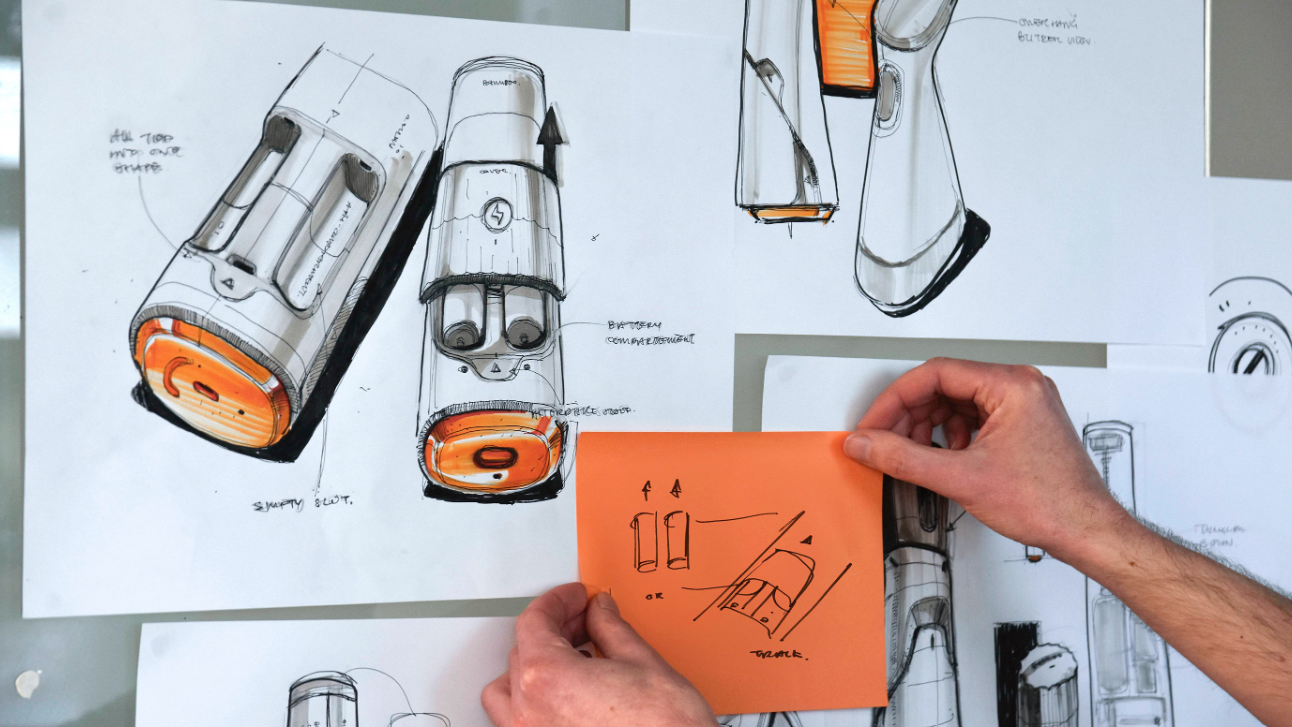

Falcon streamlines Parkinson’s treatment by replacing up to 120 monthly injections with a single implant refill. Designed for patients with reduced dexterity, it automates the refill process and provides clear, guided feedback to ensure safe and independent use. (Cambridge Consultants)